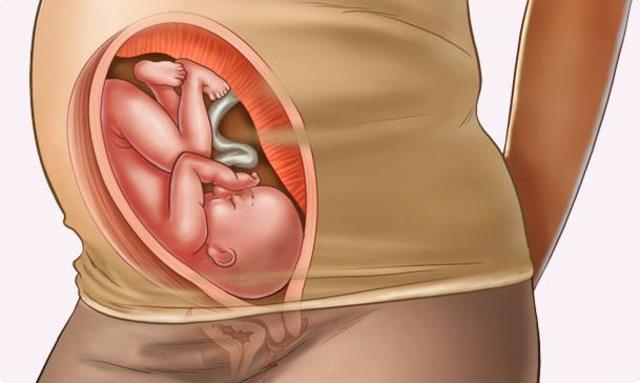

• SEMANA 27-30

SEMANA 27-30

El cerebro del bebé crece rápidamente.

El sistema nervioso se desarrolla lo suficiente para controlar algunas funciones del cuerpo.

Los párpados del bebé se pueden abrir y cerrar.

El aparato respiratorio, aunque inmaduro, produce agente tensioactivo. Esta sustancia ayuda a que los alvéolos se llenen de aire.

Los huesos del cráneo tienen una característica: están separados entre sí por surcos de tejido conectivo, las suturas

• Semana 31-34

Semana 31-34

El bebé crece rápidamente y acumula mucha grasa.

Se presenta respiración rítmica, pero los pulmones del bebé no están completamente maduros.

Los huesos del bebé están completamente desarrollados, pero son aún blandos.

El cuerpo del bebé comienza a almacenar hierro, calcio y fósforo.

En estas últimas semanas las miles de neuronas del cerebro del bebé lo ayudarán a escuchar, sentir e incluso ver formas tenues.

Sus órganos se están preparando para la vida fuera del útero.

• Semana 35 -37

Semana 35 -37

El bebé sigue aumentando de peso, pero probablemente no aumentará mucho más.

La piel no está tan arrugada a medida que se forma grasa bajo la piel.

El bebé tiene patrones de sueño definidos.

El corazón y los vasos sanguíneos de su bebé están completos.

Los músculos y los huesos están completamente desarrollados.

• Semana 38-40

Semana 38-40

El lanugo ha desaparecido excepto en la parte superior de los brazos y los hombros.

Las uñas pueden extenderse más allá de las puntas de los dedos.

Se presentan pequeños brotes mamarios en ambos sexos.

El cabello de la cabeza ahora es grueso y más denso.